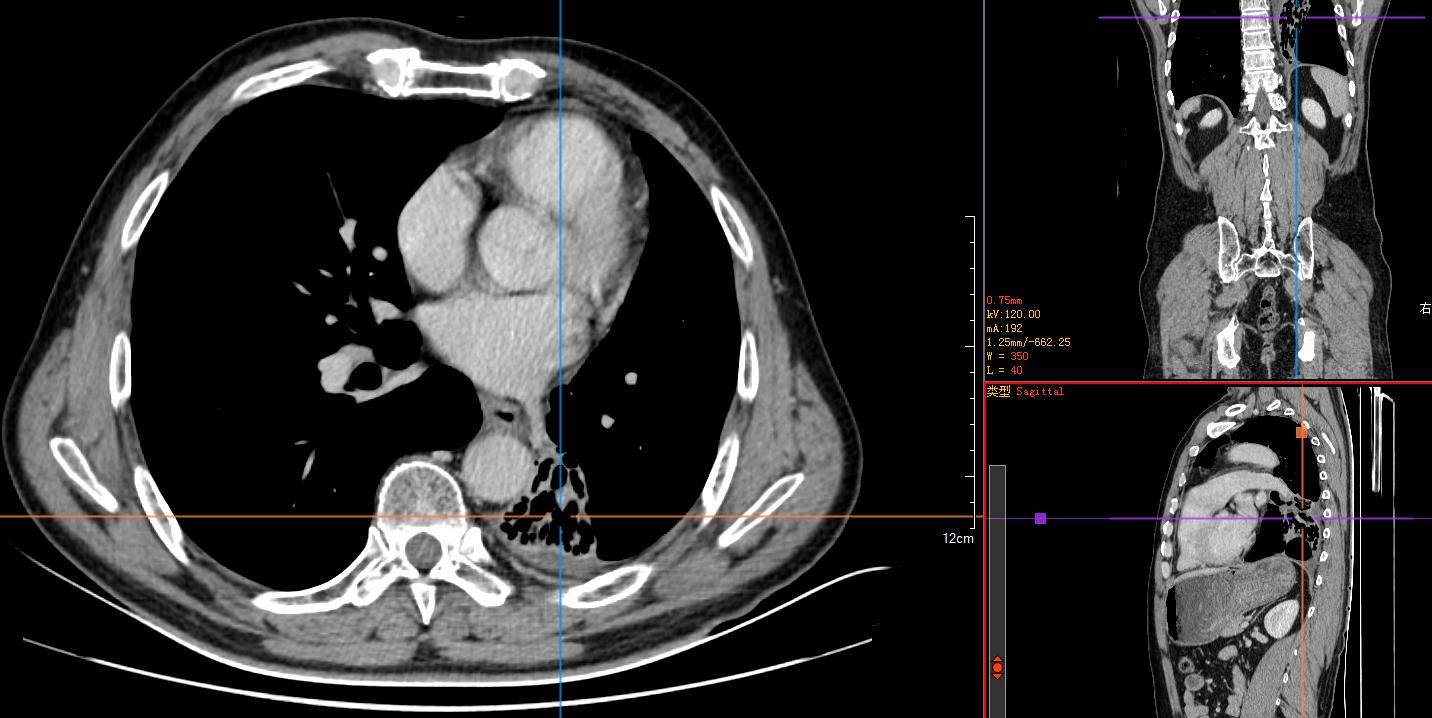

2)胸腹部平扫+增强CT示:左肺占位性肿块伴阻塞性肺不张,纵膈淋巴结肿大,建议穿刺活检。左肺动脉分支动脉瘤;右肾小错构瘤可能;双侧股骨颈小滑膜疝。